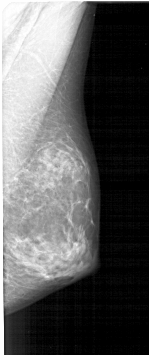

A_1379_1.LEFT_CC

LEFT_CC LINES 5086 PIXELS_PER_LINE 2596 BITS_PER_PIXEL 12 RESOLUTION 43.5 OVERLAY